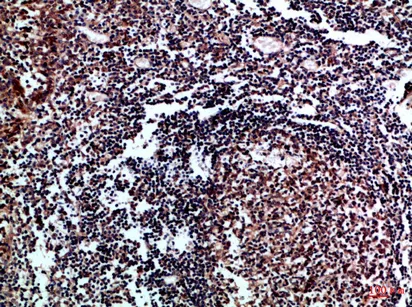

Cystatin B Rabbit Polyclonal Antibody

Cat: APRab09694